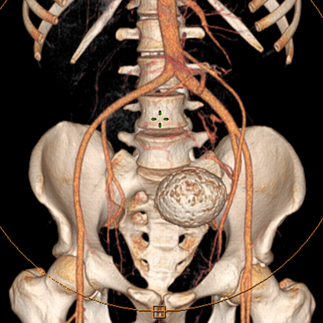

On physical examination, a nontender, firm mass was easily palpable in the left lower quadrant extending to the pelvic brim. Computed tomography Scan of the chest, abdomen, and pelvis revealed a pancake kidney with a large mass in the left moiety, measuring 150X110X200 mm. The tumor extended into the isthmus and appeared to abut or extend into the inferior right moiety, at the site of fusion of both moieties, just below the aortic bifurcation, with a macrocalcification (Figure 1). Bilateral renal arteries were arising from the ipsilateral external iliac arteries (Figure 2) with an accessory renal artery on the right side from the aorta. no metastasis was found.

Figure 2 Scannographic reconstruction showing the vascularization of the kidney mainly on the iliac axes.